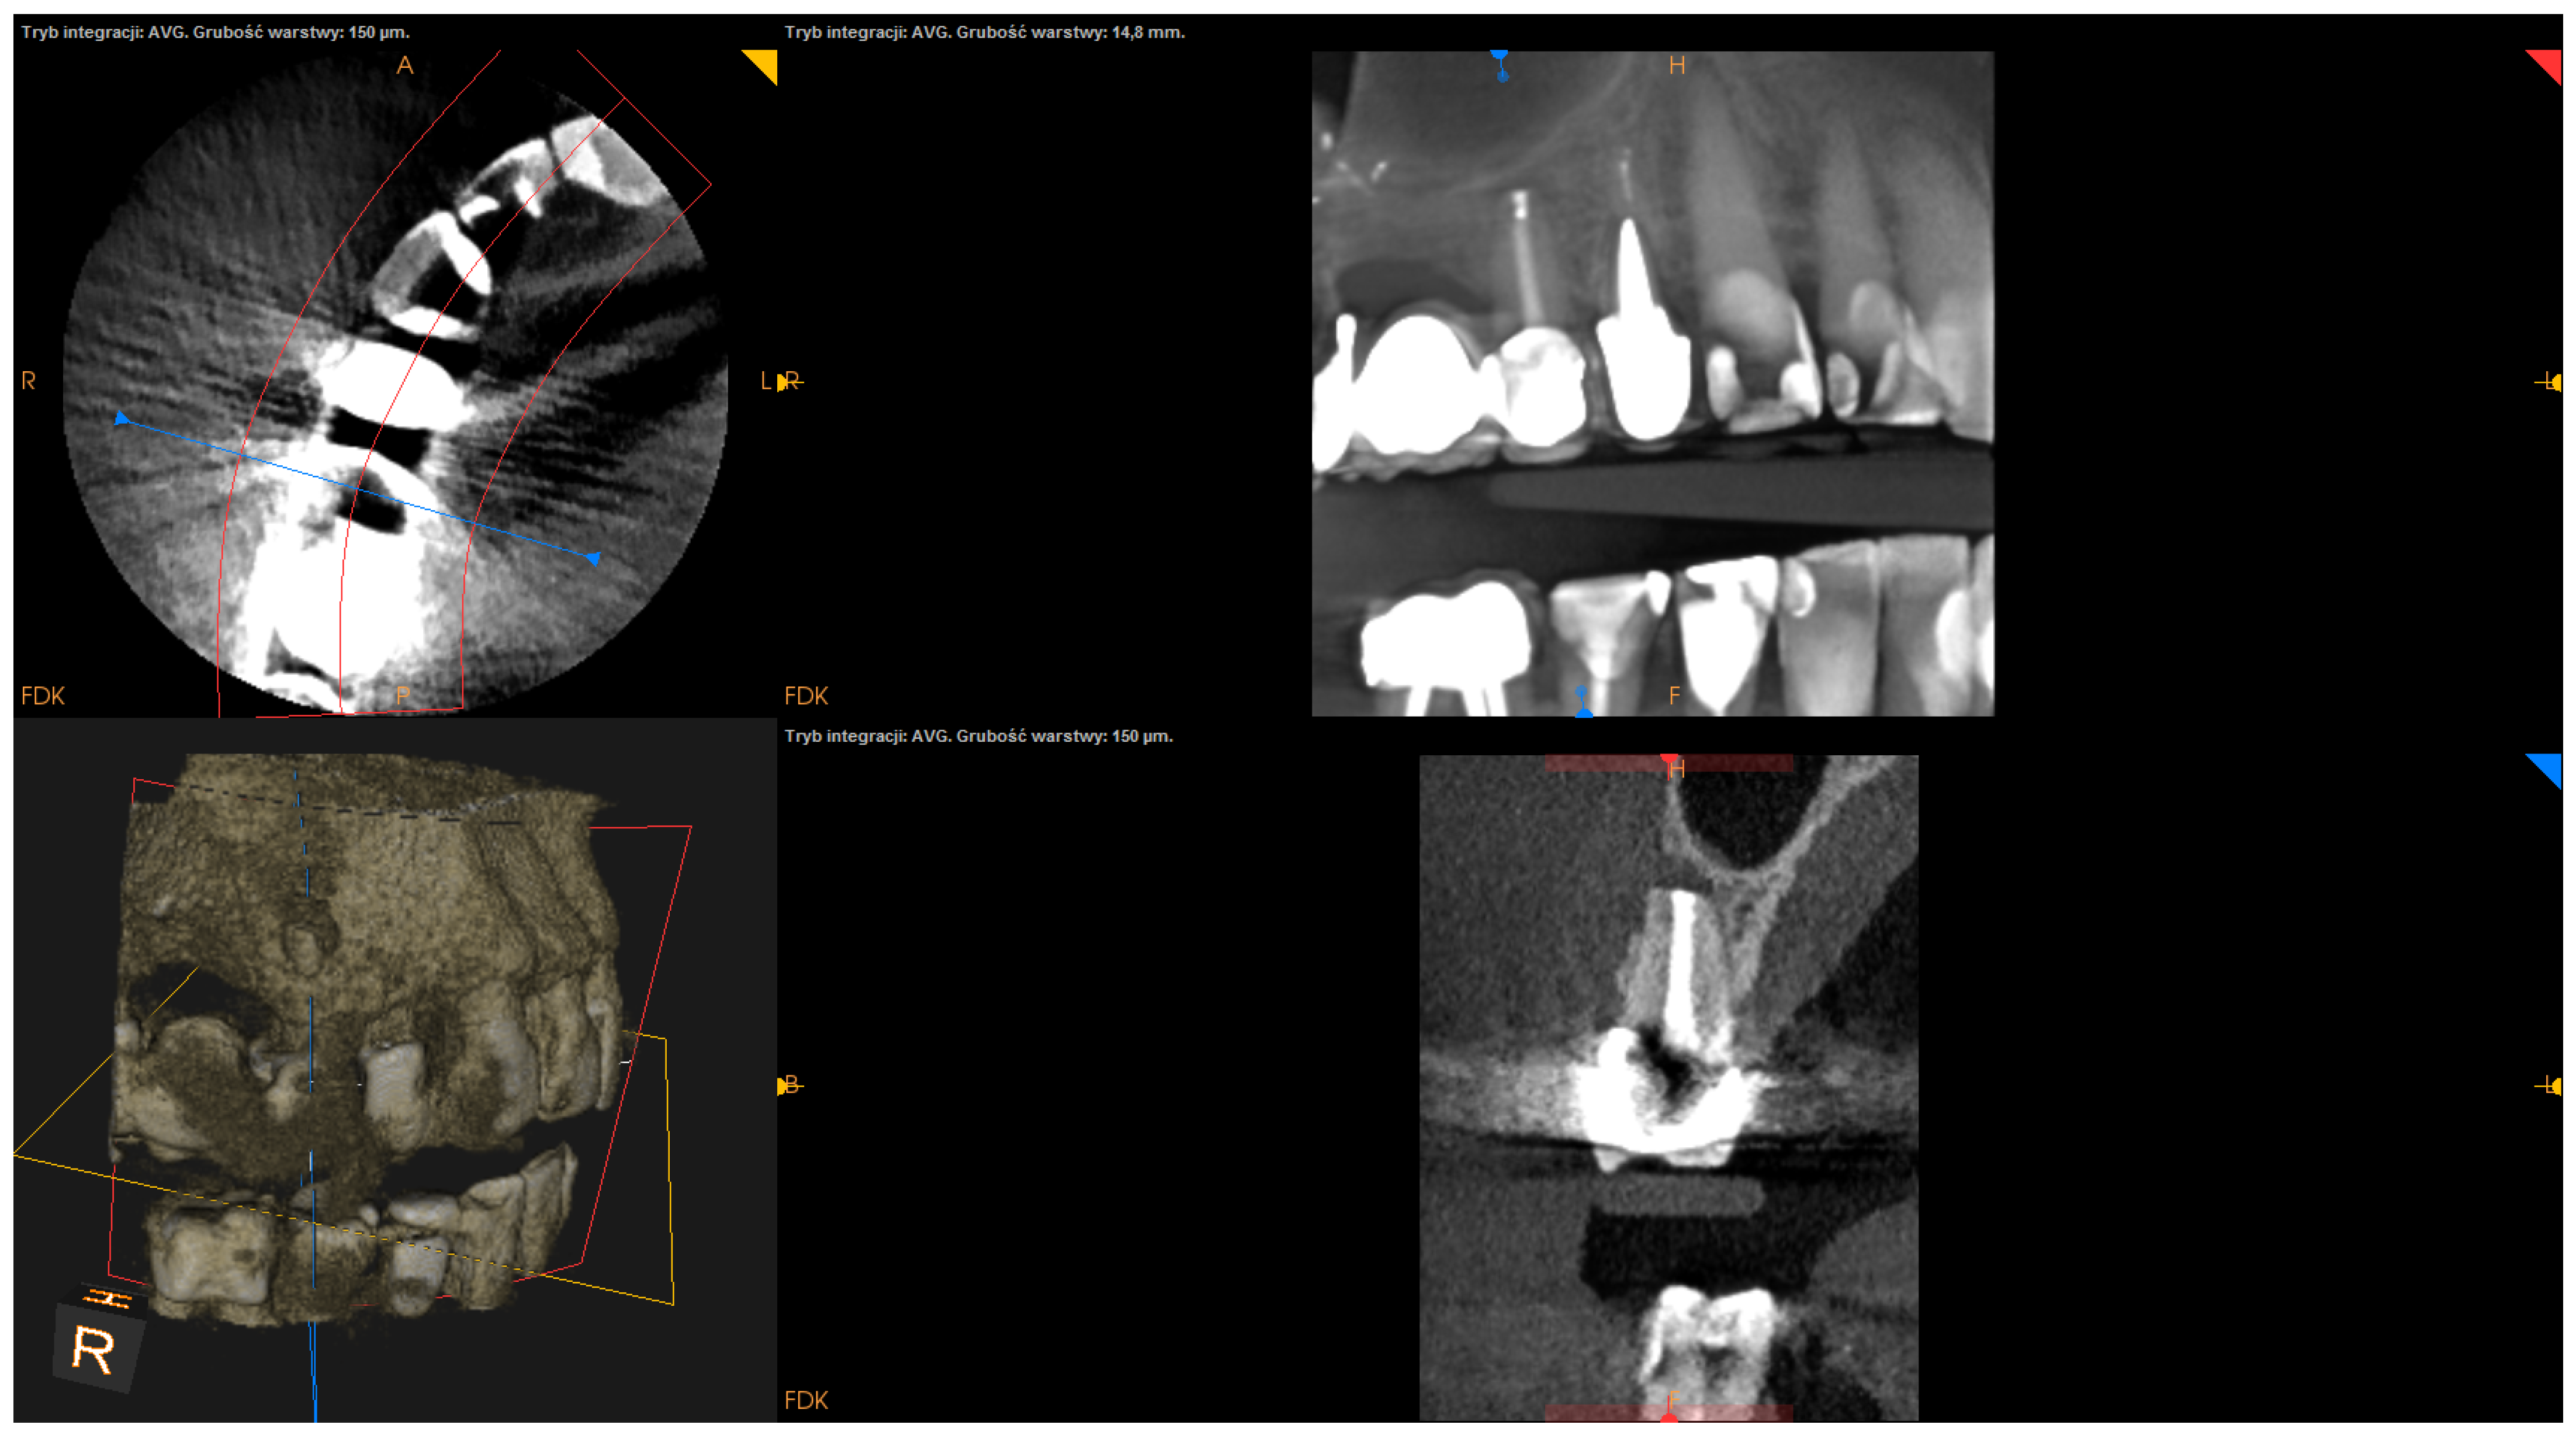

- The status of radiographic healing (rated in all sections, according to modified PENN 3D criteria [28]) was classified as complete healing (Figure 1), incomplete healing (Figure 2), uncertain healing (Figure 3), or unsatisfactory healing (Figure 4).

Figure 3. CBCT image (CS 8100 3D Carestream Dentalⓡ) example of uncertain healing based on PENN 3D criteria. Non-English annotations present software technicalities (AVG integration mode and layer thickness).